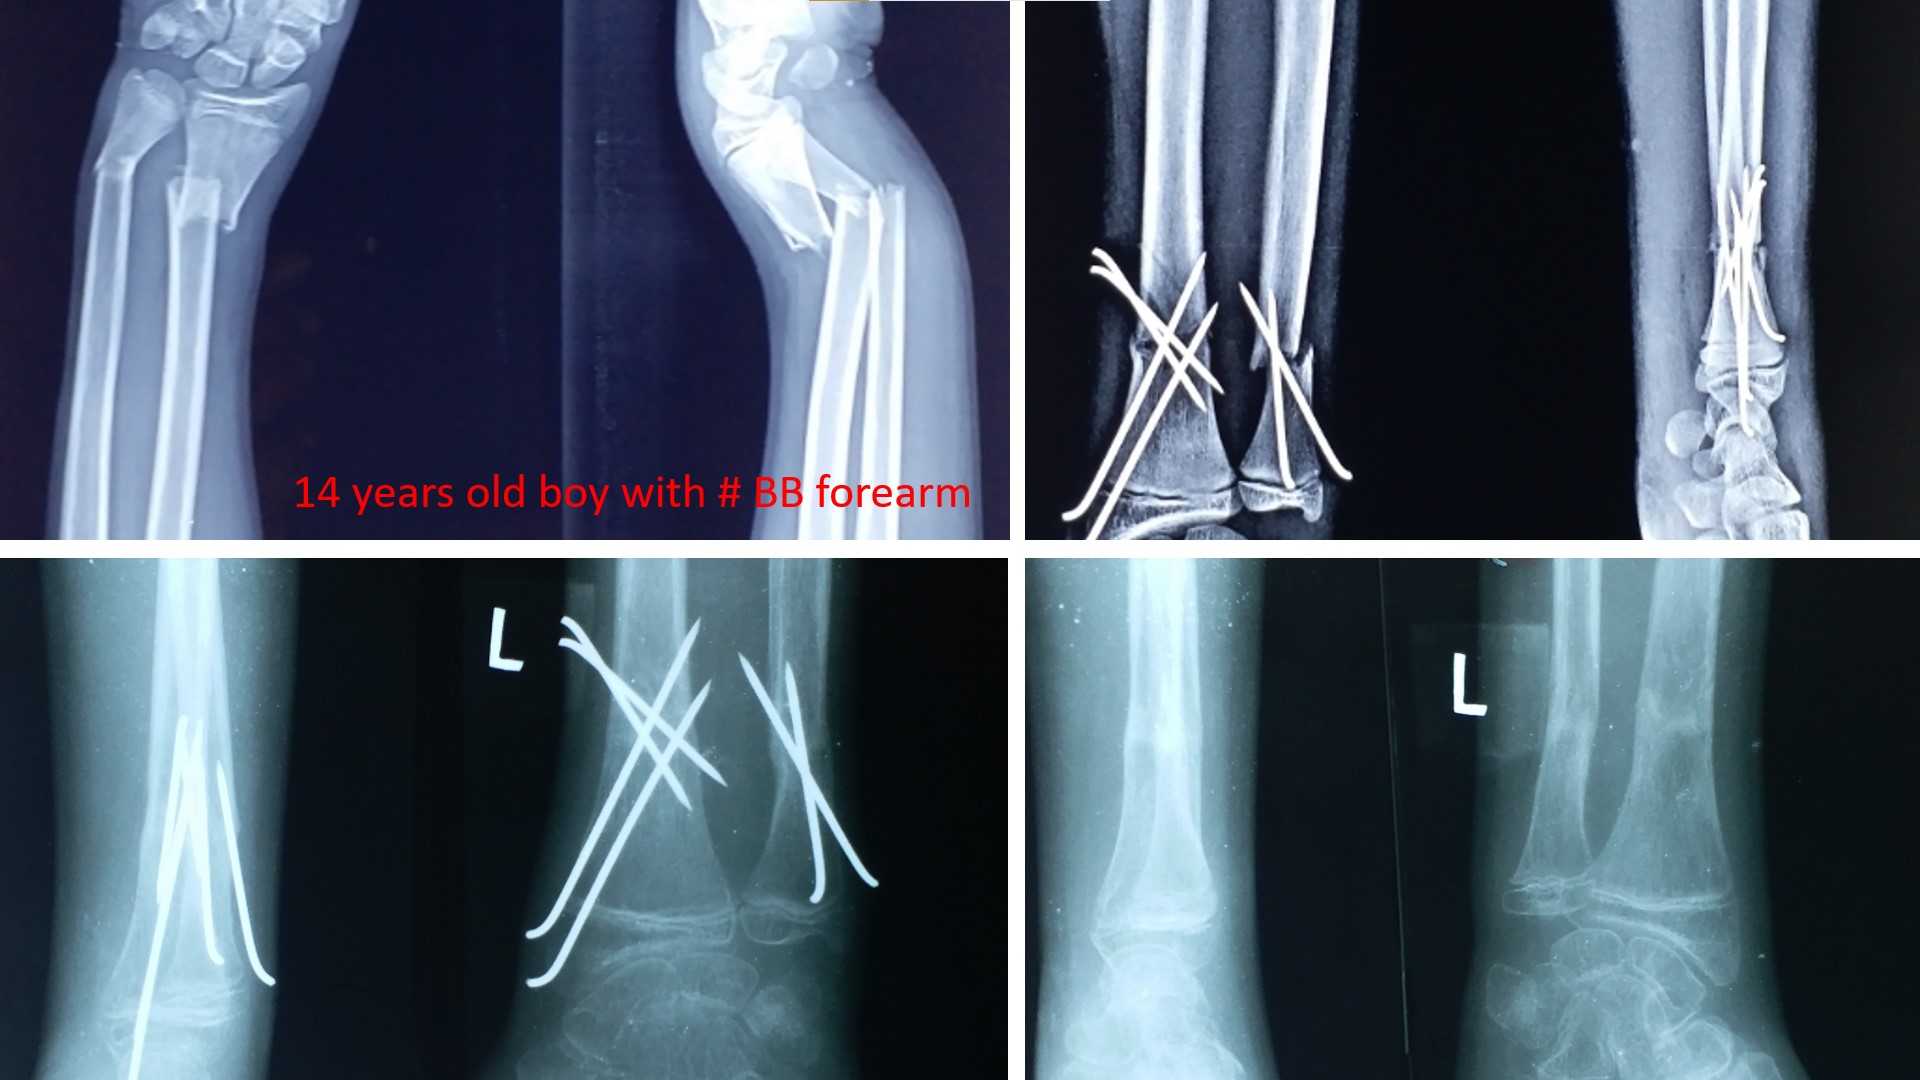

FRACTURE LOWER 3RD FOREARM